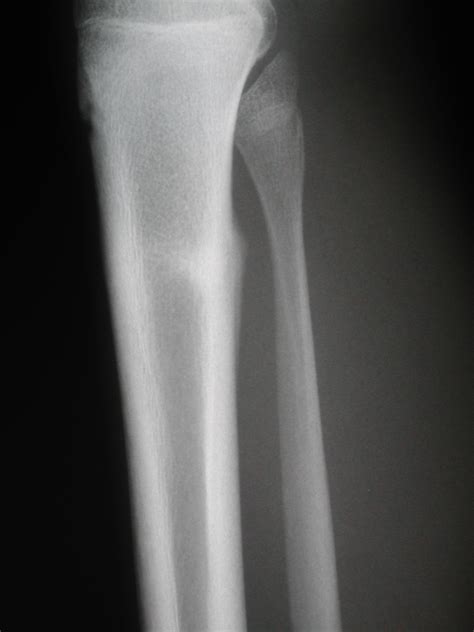

Diagnosis and Clinical Assessment

If you suspect you have a stress fracture, it is vital to seek professional medical advice. A healthcare provider will typically perform a physical examination, assessing the site of tenderness and your range of motion. Because stress fractures are often so small, they do not always appear on standard X-rays, especially in the first few weeks of the injury.

Doctors may suggest more sensitive imaging techniques if clinical symptoms remain high despite a clear X-ray. An MRI is often considered the "gold standard" for diagnosing a stress fracture tibia because it can detect bone marrow edema (swelling inside the bone), which is an early sign of stress-related injury before a fracture line even forms.